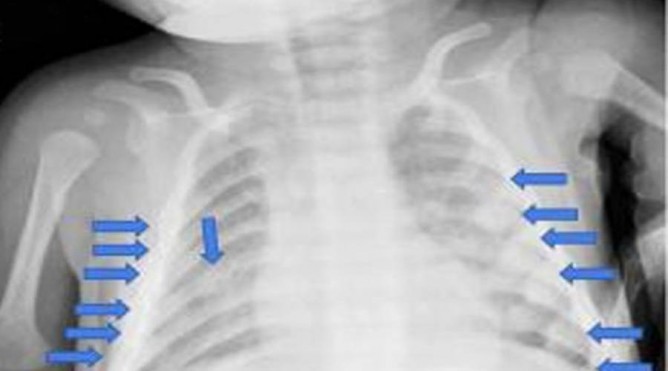

இந்நிலையில் குழந்தையை சோதனை செய்த மருத்துவர்கள் குழந்தை கடுமையாக தாக்கப்பட்டுள்ளது என்றும், தோள்பட்டை, கை, கால் என்று குழந்தையின் 28 எலும்புகள் உடைக்கப்பட்டுள்ளது என்றும் தெரிவித்தனர்.